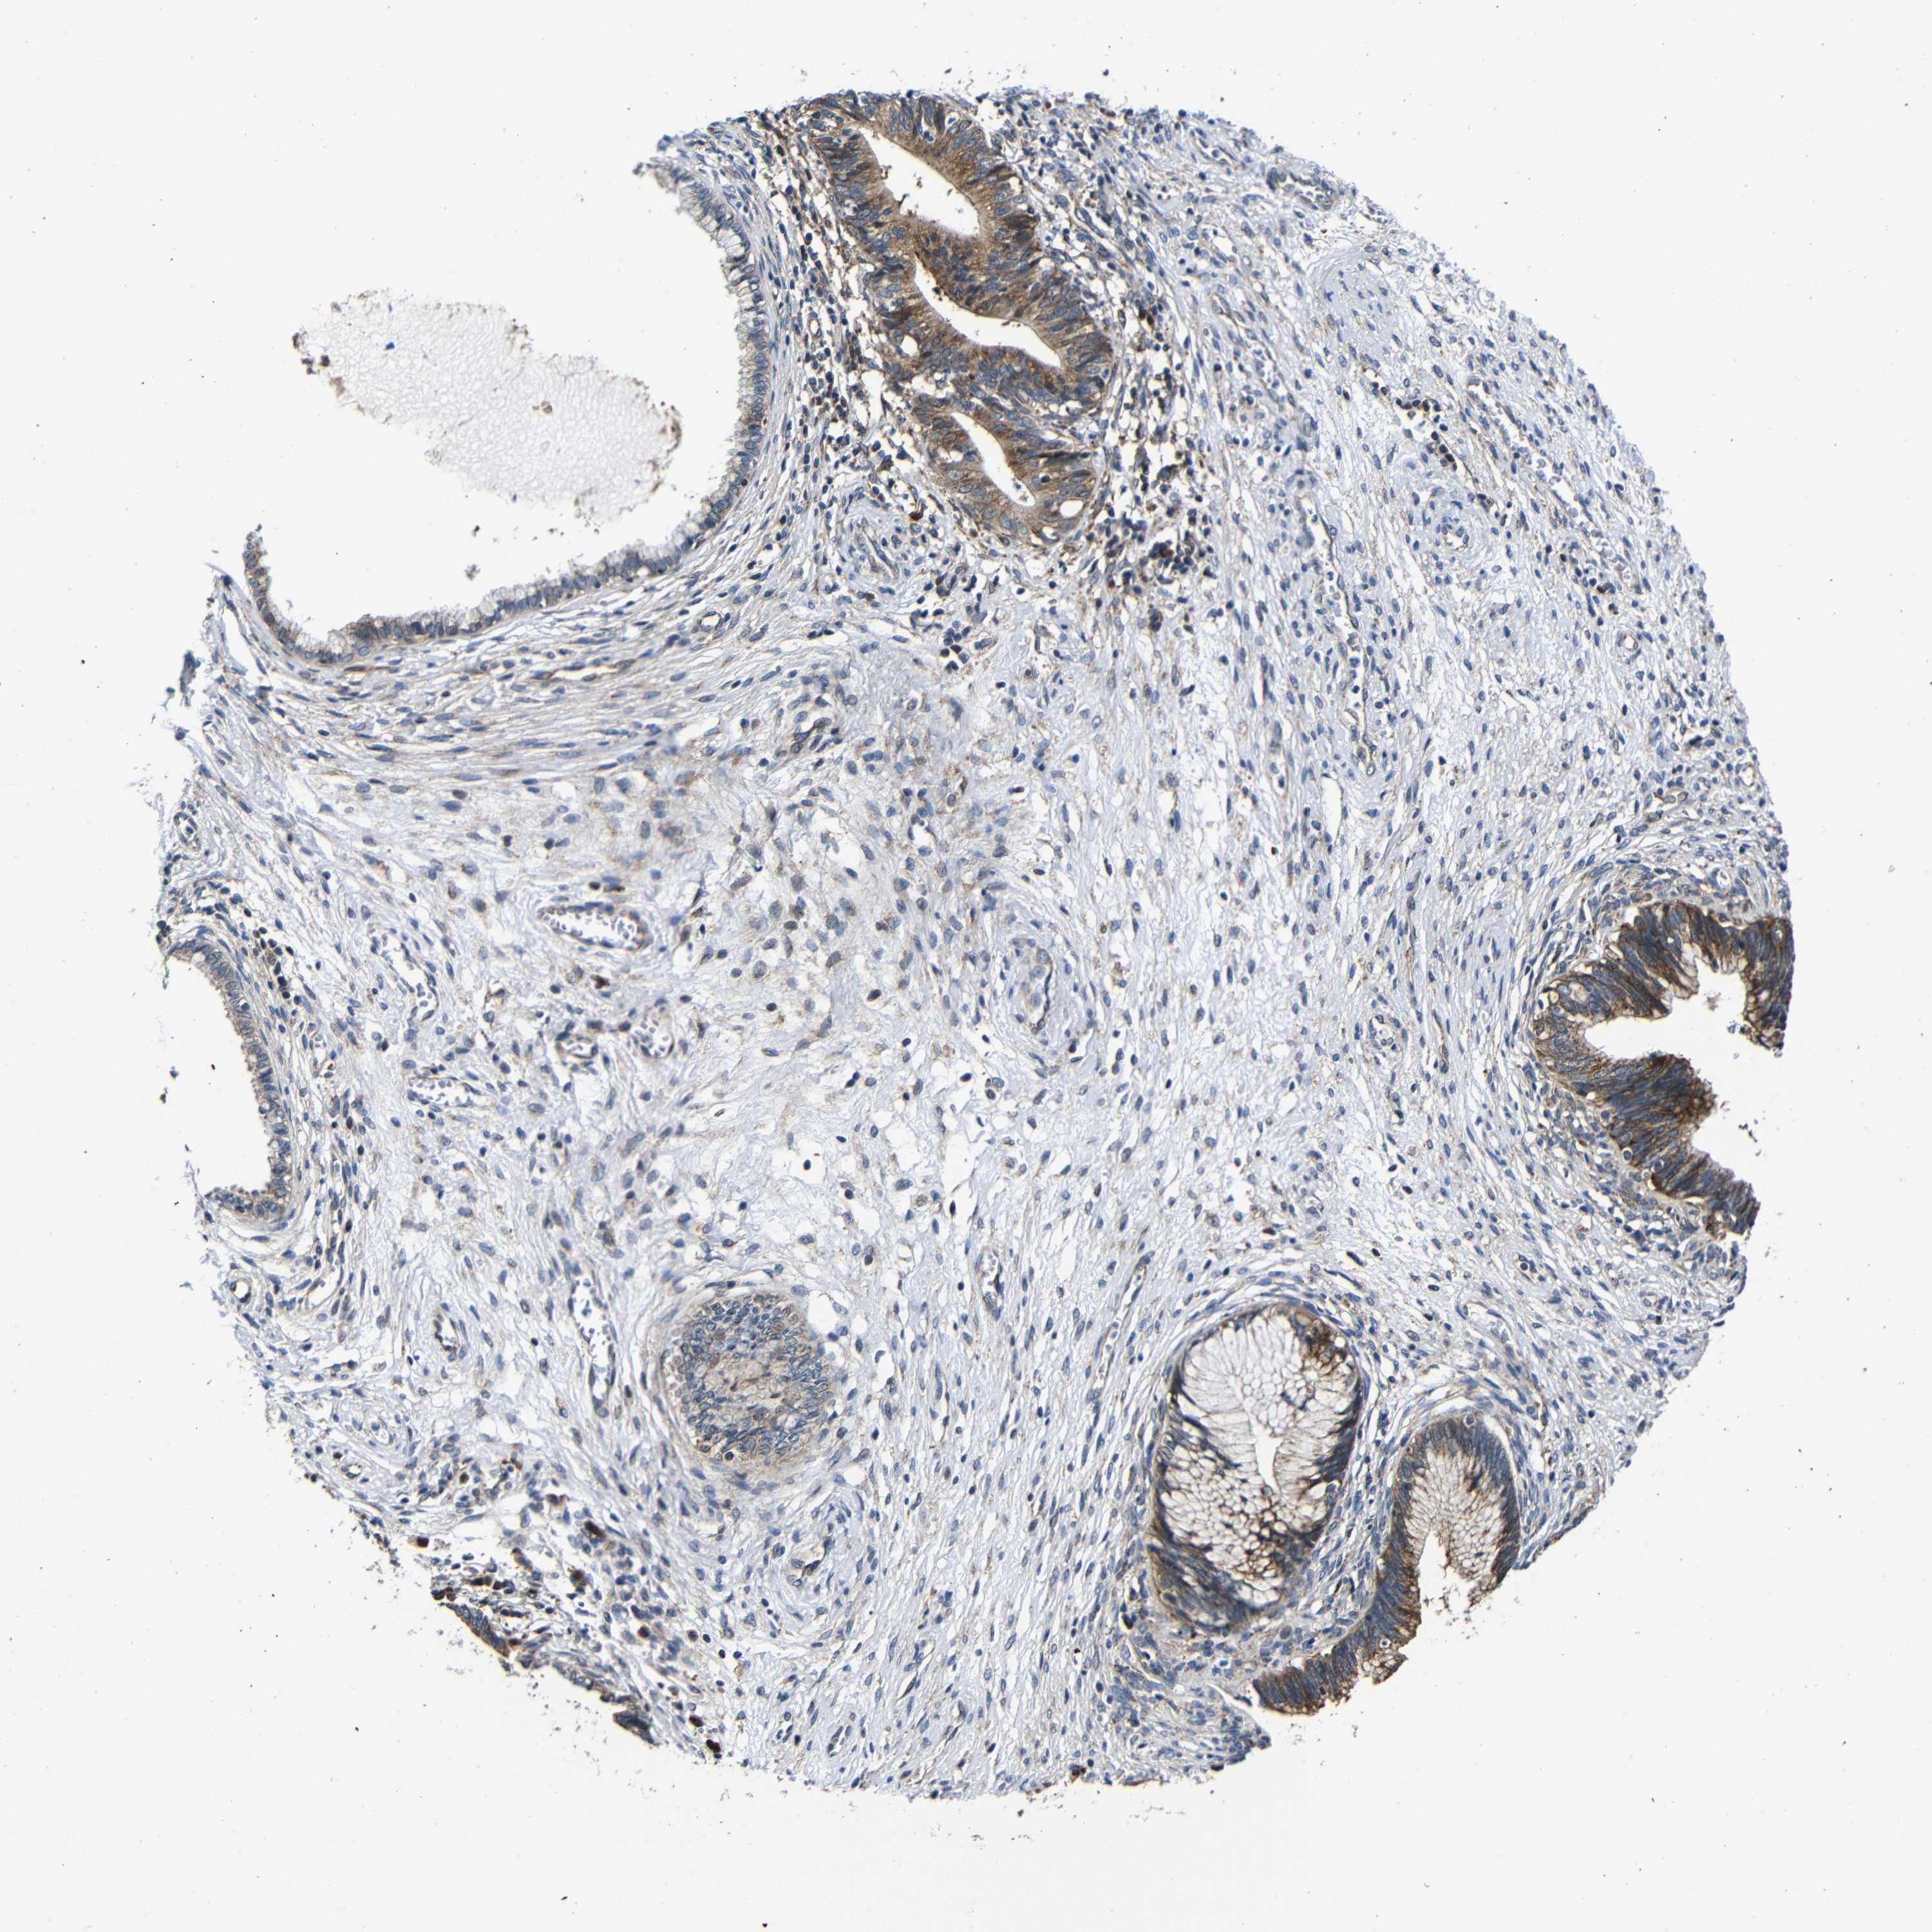

CERVICAL CANCER - Protein expressioni

A mouse-over function shows sample information and annotation data. Click on an image to view it in a full screen mode. Samples can be filtered based on level of antibody staining by selecting one or several of the following categories: high, medium, low and not detected. The assay and annotation is described here.

Note that samples used for immunohistochemistry by the Human Protein Atlas do not correspond to samples in the TCGA dataset.

Antibody stainingi

Antibody staining in the annotated cell types in the current human tissue is reported as not detected, low, medium, or high, based on conventional immunohistochemistry profiling in selected tissues. This score is based on the combination of the staining intensity and fraction of stained cells.

Each image is clickable and will lead to virtual microscopy that enables deeper exploration of all samples and also displays staining intensity scores, fraction scores and subcellular localization as well as patient and tissue information for each sample.

Antibody CAB012476

Staining

High

Medium

Low

Not detected

Intensity

Strong

Moderate

Weak

Negative

Quantity

>75%

75%-25%

<25%

None

Location

Nuclear

Cytoplasmic/membranous

Cytoplasmic/membranous,nuclear

Squamous cell carcinoma, NOS

Adenocarcinoma, NOS